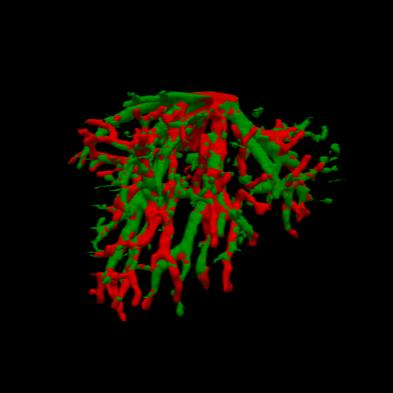

Manually segmenting the hepatic vessels from Computer Tomography (CT) is far more expertise-demanding and laborious than other structures due to the low-contrast and complex morphology of vessels, resulting in the extreme lack of high-quality labeled data. Without sufficient high-quality annotations, the usual data-driven learning-based approaches struggle with deficient training. On the other hand, directly introducing additional data with low-quality annotations may confuse the network, leading to undesirable performance degradation. To address this issue, we propose a novel mean-teacher-assisted confident learning framework to robustly exploit the noisy labeled data for the challenging hepatic vessel segmentation task. Specifically, with the adapted confident learning assisted by a third party, i.e., the weight-averaged teacher model, the noisy labels in the additional low-quality dataset can be transformed from "encumbrance" to "treasure" via progressive pixel-wise soft-correction, thus providing productive guidance. Extensive experiments using two public datasets demonstrate the superiority of the proposed framework as well as the effectiveness of each component.

翻译:将来自计算机地形学(CT)的肝脏船只人工分割,由于船只的低调和复杂形态,由于低调和复杂的形态,造成极端缺乏高质量的标签数据,因此比其他结构更需要专门知识和难度大得多。如果没有足够的高质量的说明,通常的数据驱动的基于学习的方法就会与不足的培训斗争。另一方面,直接引进低质量说明的额外数据可能会混淆网络,导致不良的性能退化。为了解决这一问题,我们提议建立一个新的、由教师协助的、有说服力的、有说服力的学习框架,为具有挑战性的肝脏船只分解任务强有力地利用响亮的标签数据。具体地说,在第三方(即加权平均教师模式)的协助下,经过变通的自信学习后,额外低质量数据集中的噪音标签可以从“阻力”转变为“压力”,通过渐进式的像素方法的软校正,从而提供富有成效的指导。使用两个公共数据集进行的广泛实验,显示了拟议框架的优越性以及每个组成部分的效能。